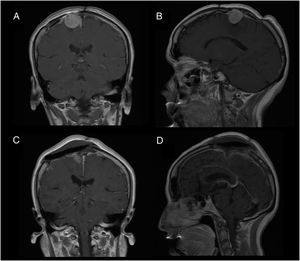

Patient 2Our second patient was a 49-year-old woman with history of interhemispheric meningioma, which was treated surgically 20 years previously. She underwent surgery after presenting tumour recurrence (Fig. 2A and B); the procedure was uneventful and complete tumour resection was achieved (Fig. 2C and D). Upon awakening, the patient presented normal consciousness but was unable to move the left side of her body (muscle strength 1/5). CT angiography ruled out complications of venous drainage. After a short rehabilitation period, the patient recovered baseline muscle strength (5/5); she was discharged after 10 days with no other complications.